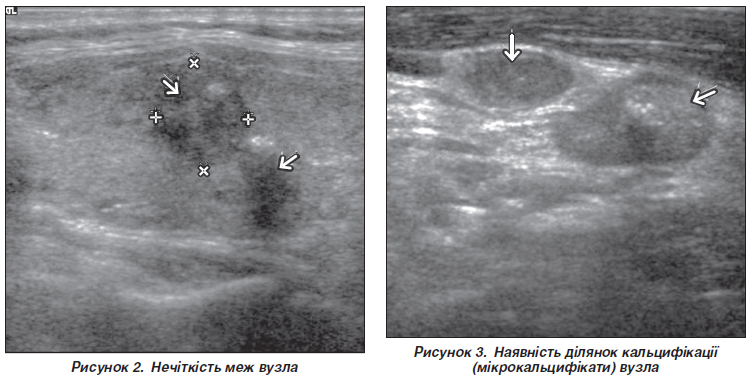

Актуальність. Через низьку чутливість і специфічність ультразвукового дослідження шиї при оцінці лімфатичних вузлів центрального колектора необхідно знайти альтернативні шляхи для прогнозування метастазів у центральні лімфатичні вузли шиї (CLNM) у пацієнтів з папілярним раком щитоподібної залози (ПРЩЗ). Мета: розробити прогностичну модель для оцінки ризику місцевого метастазування папілярного раку щитоподібної залози на основі доопераційних ультразвукових і демографічного предикторів. Матеріали та методи. Проведено ретроспективне моноцентрове когортне дослідження. Опрацьовано дані 401 пацієнта, яких було прооперовано з приводу ПРЩЗ. Основна група — 179 хворих, у яких виявлено CLNM на патогістологічному дослідженні (ПГД). Група порівняння — 222 пацієнти без метастазів за результатами ПГД. При проведенні аналізу враховувались як фактори ризику такі ознаки: субкапсулярне розташування пухлини; розмір; нечіткість меж; наявність ділянок кальцифікації (мікрокальцифікати); вік пацієнта. Критерії включення: цитологічно підтверджений ПРЩЗ на доопераційному етапі; оперовані пацієнти (тиреоїдектомія/гемітиреоїдектомія та центральна лімфатична дисекція шиї). Критерії виключення: операції в ділянці шиї у анамнезі; пацієнти з багатофокусним ураженням ЩЗ. Результати. За допомогою програми StatPlus було отримано таке логістичне рівняння: y = –1,839 – 0,037 × × X1 + 0,097 × X2 + 1,123 × X3 + 1,198 × X4 + 0,692 × X5, де X1, X2, X3, X4, X5 — вік (років), розмір (мм), субкапсулярне розташування (наявність), нечіткість меж (наявність), кальцифікати (наявність) відповідно. Отримана прогностична модель забезпечувала такі операційні характеристики при уточненні порогового значення для Р, яке дорівнює 0,44 (вирішальне правило X > T): чутливість — 75,4 %, специфічність — 79,3 %, діагностична ефективність — 75,1 %. З метою оцінки якості моделі було виконано процедуру ROC-аналізу. Отримані такі дані: площа під кривою (AUC) = 0,797 (95% ДІ: 0,753–0,841), що відповідає добрій якості моделі, індекс Юдена (J) = 0,5155. Перевірка якості моделі на контрольній групі зі 100 осіб дала такі результати: чутливість — 72,2 %, специфічність — 76,1 %, діагностична ефективність — 75,8 %. Висновки. Застосування математичної моделі на основі ультразвукових предикторів і віку пацієнта дає змогу прогнозувати наявність локальних метастазів ПРЩЗ на доопераційному етапі з діагностичною ефективністю 75,8 %. Жодна прогностична модель не дає 100% точності прогнозу. У виборі тактики лікування слід враховувати додаткові фактори впливу (опромінення в анамнезі, обтяжений сімейний анамнез тощо) на конкретного пацієнта.